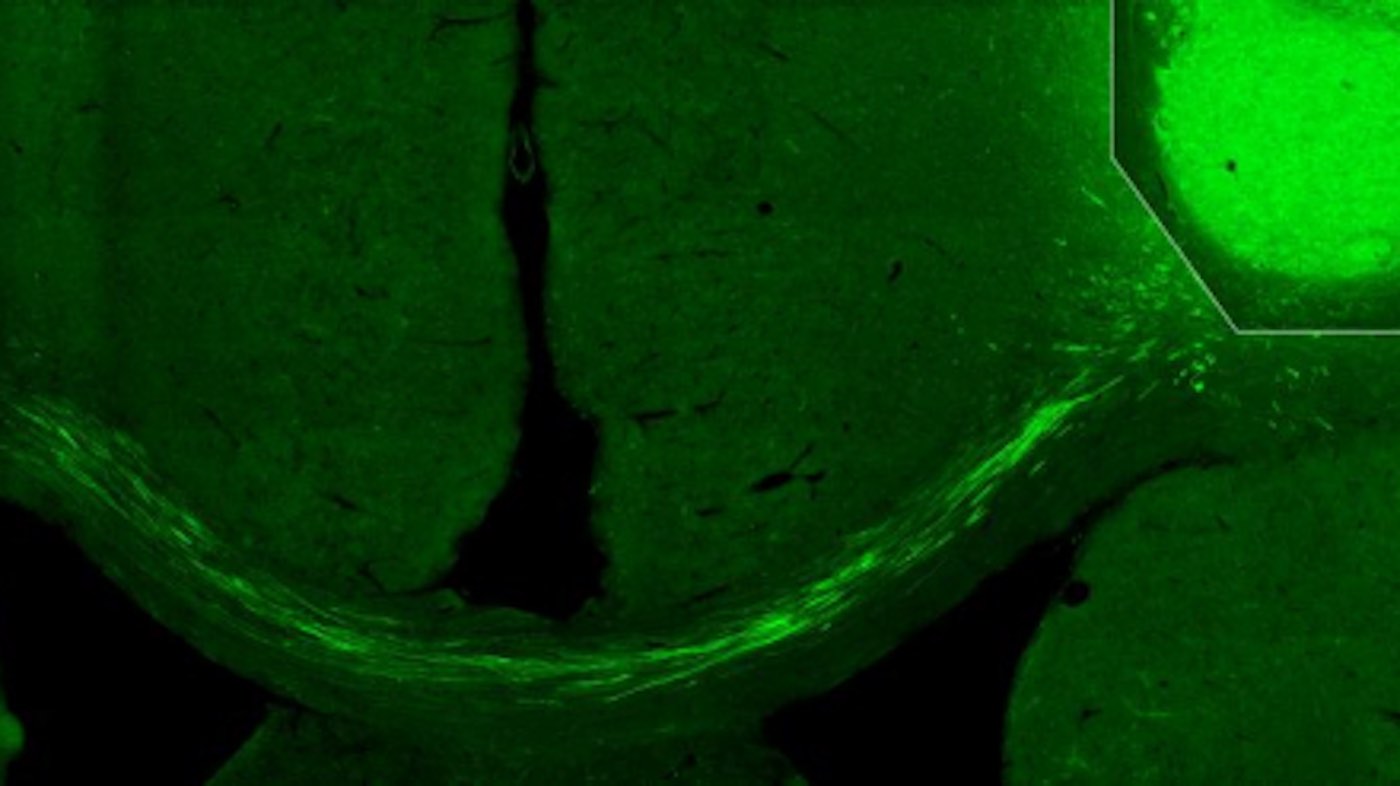

“We have used tracking techniques, electron microscopy and other methods, such as light to switch off activity in the transplanted cells, as a way to show that they really have connected correctly in the damaged nerve circuits. We have been able to see that the fibers from the transplanted cells have grown to the other side of the brain, the side where we did not transplant any cells, and created connections. No previous study has shown this,” says Kokaia, who—even though he and colleague senior professor Olle Lindvall have studied the brain for several decades—was surprised by the results.

The researchers have used human skin cells that have been reprogrammed in the laboratory to become nerve cells. They were then transplanted into the cerebral cortex of rats, in the part of the brain that is most often damaged after a stroke. Now the researchers will undertake further studies.

Photo by Lund University.